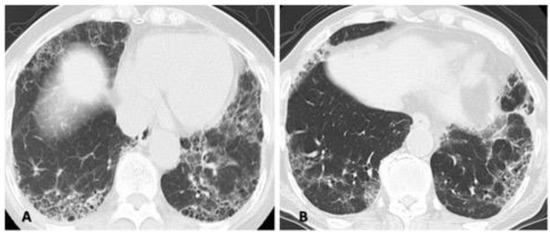

4.2. Disease Behavior

4.3. Predictors of ILD Progression and Prognostic Factors

4.5. Therapeutic Assessment of the Chronic Course of RA-ILD

4.5.2. Presence of Progressive ILD Itself despite Stable Arthritis